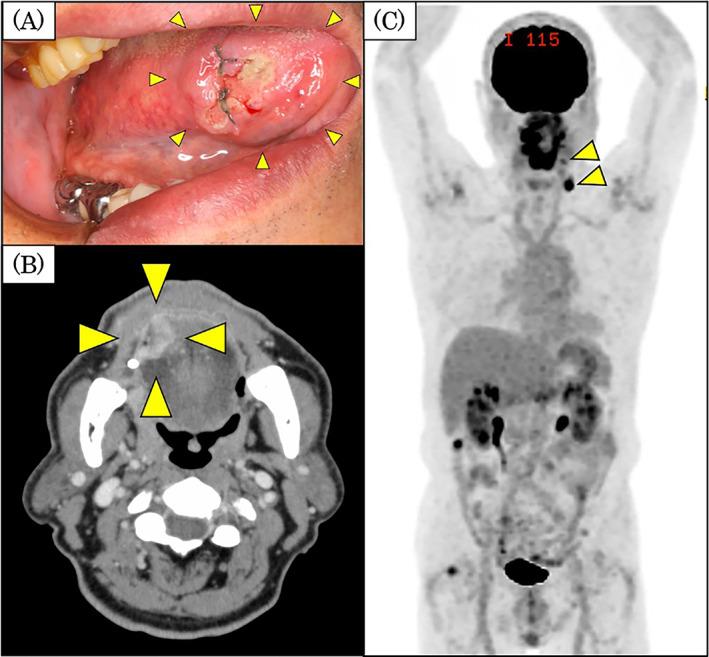

Hodgkin lymphoma (HL) is diagnosed definitively by biopsy, and treatment is based on stage. Owing to the nature of the disease, post-treatment efficacy is determined mainly by fluorodeoxyglucose-positron emission tomography/computed tomography, and the efficacy of treatment is not confirmed by histopathology. We report a case of tongue cancer after treatment for HL, in which a post-treatment lymph node with complete remission was histopathologically confirmed by neck dissection.

The patient was a 74-year-old man who was referred to our hospital for cancer on the right side of his tongue. He had previously undergone chemotherapy for HL involving the right side of his neck and achieved complete remission. Because he had cT3N2cM0 tongue cancer, glossectomy and bilateral neck dissection were performed. Surprisingly, histopathological examination revealed that there was neither metastatic lymph nodes nor lymphoma cells in his right neck. Moreover, there was no lymphatic structure in his remnant lymph nodes.

This was a rare case in which complete remission of HL was confirmed by histopathological analysis. The absence of lymph node structure and lymphatic flow led to contralateral neck lymph node metastases of tongue cancer.